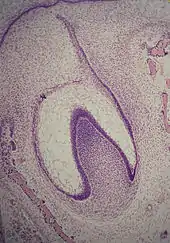

A: organe de l'émail avec la lame dentaire

B: papille dentaire

C: follicule dentaire.

La formation d'une dent commence donc par un agrégat cellulaire, le germe dentaire[2], dérivant de l'ectoderme issu du premier arc branchial de la crête neurale[1],[3],[4]. Ce tissu d'origine ectoblastique va se transformer en un tissu mésenchymateux appelé ectomésenchyme ou mésenchyme ectodermique. Le germe dentaire est divisé en trois parties : le bourgeon dentaire (ou organe de l'émail ou encore organe adamantin), issu de l'ectoderme, la papille dentaire et le follicule dentaire, issus du mésenchyme.